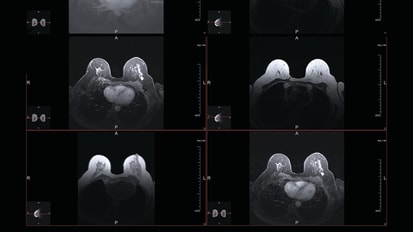

Ushering Breast Cancer Into a New Era of Collaborative Care News

Ushering Breast Cancer Into a New Era of Collaborative Care

Award-winning clinician-researcher Heather McArthur, M.D., M.P.H., shares her vision for Simmons’ Breast Cancer Program.

Clarifying the Mechanics of Brain Metastasis in Breast Cancer News

Clarifying the Mechanics of Brain Metastasis in Breast Cancer

A new study reveals how breast cancer metastasizes in the brain and how metabolic diversity and plasticity dictate its spread.

Response to Hormone Therapy Predicts Radiation Resistance in ER+ Breast Cancer News

Response to Hormone Therapy Predicts Radiation Resistance in ER+ Breast Cancer

How estrogen receptor-positive (ER+) breast cancer responds to hormone therapy may hold keys to understanding how it will respond to radiation therapy, and an experimental drug that increases the effectiveness of hormone therapy also overcomes radiation resistance in breast cancer, a study by UT Southwestern Medical Center researchers shows.